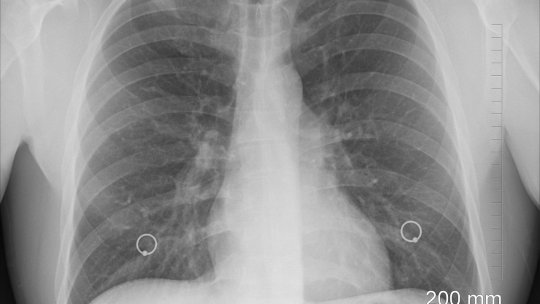

200 de pacienţi cu tuberculoză au fost diagnosticaţi în cadrul unui proiect gratuit de depistare precoce, screening,...